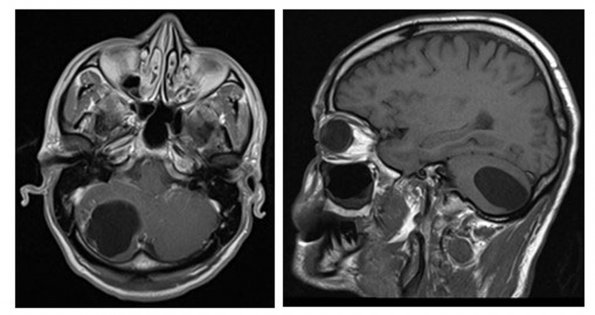

9A Neurocysticercosis, racemose (AANP DSS 2018 case 11) MRI

MRI examination showed a large cyst in the right cerebellar hemisphere.